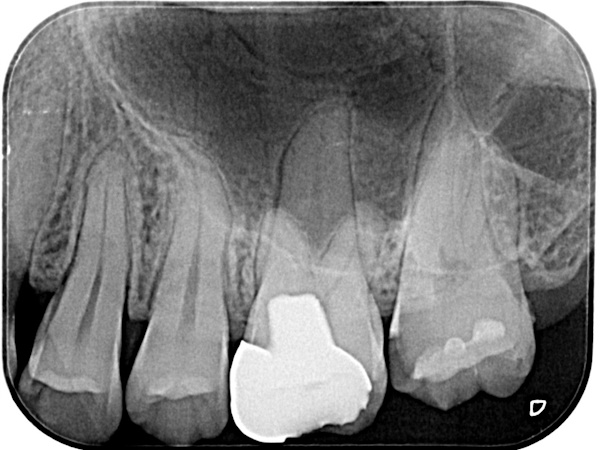

初診時